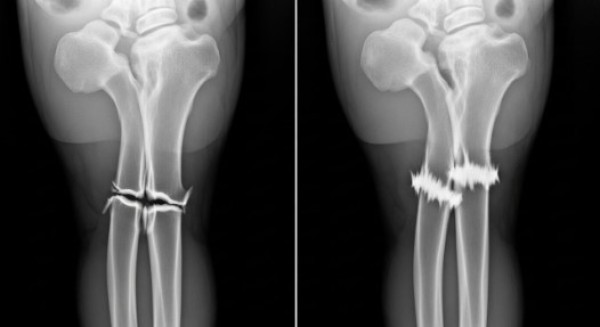

João taxista tem pernas amputadas e família pede ajuda para cadeira elétrica João taxista tem pernas amputadas e família pede ajuda para cadeira elétrica

Tri-Fronteira - João taxista tem pernas amputadas e família pede ajuda para cadeira elétrica

O taxista João Maria Caetano de Souza, conhecido na região da tri-fronteira, enfrenta um dos momentos mais difíceis da vida após ter as duas pernas amputadas em dezembro, em de ...